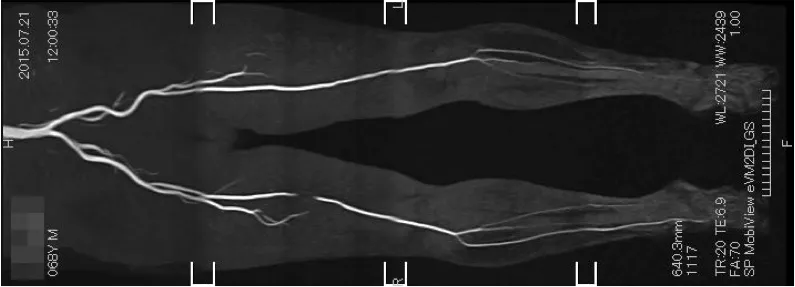

外科では視触診(足の皮膚温、脈がとれるかどうか)、ABI※測定、血液の流れの波形の解析などを行い、血管の閉塞が疑われる場合はCTやMRIによる血管撮影に進みます。 その結果により薬物治療を選択するか、カテーテル治療を含む手術的治療を行うかを提示します。 現状では当院での手術治療は困難ですので、手術適応のある場合は他の専門医療機関に紹介しています。 前述した通り動脈硬化症は全身病ですので、心臓や脳の血管も同程度に進行している場合もあることから、状況に応じ循環器内科や脳神経外科の先生にも診察をお願いする場合もあります。

- MRIによる血管撮影